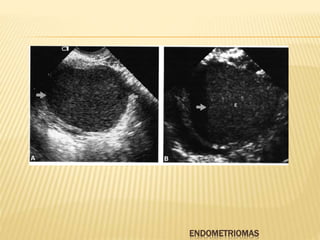

ENDOMETRIOMA

 Frecuentemente son asitomáticos y múltiples

 Masa predominantemente quistita , unilocular o

multilocular, bordes bien definidos

 Ecos internos de bajo nivel, difusamente

homogéneas, apreciándose mucho mejor con

ecografía transvaginal

 El aspecto puede ser similar a un quiste

hemorrágico sin embargo este se asocia a un

patrón reticular y frecuentemente con liquido en

el fondo de saco

ENDOMETRIOMAS